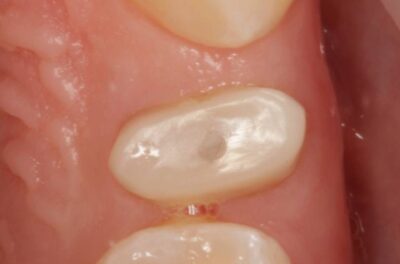

Специализация: терапия(эндодонтия), ортопедия, имплантология.